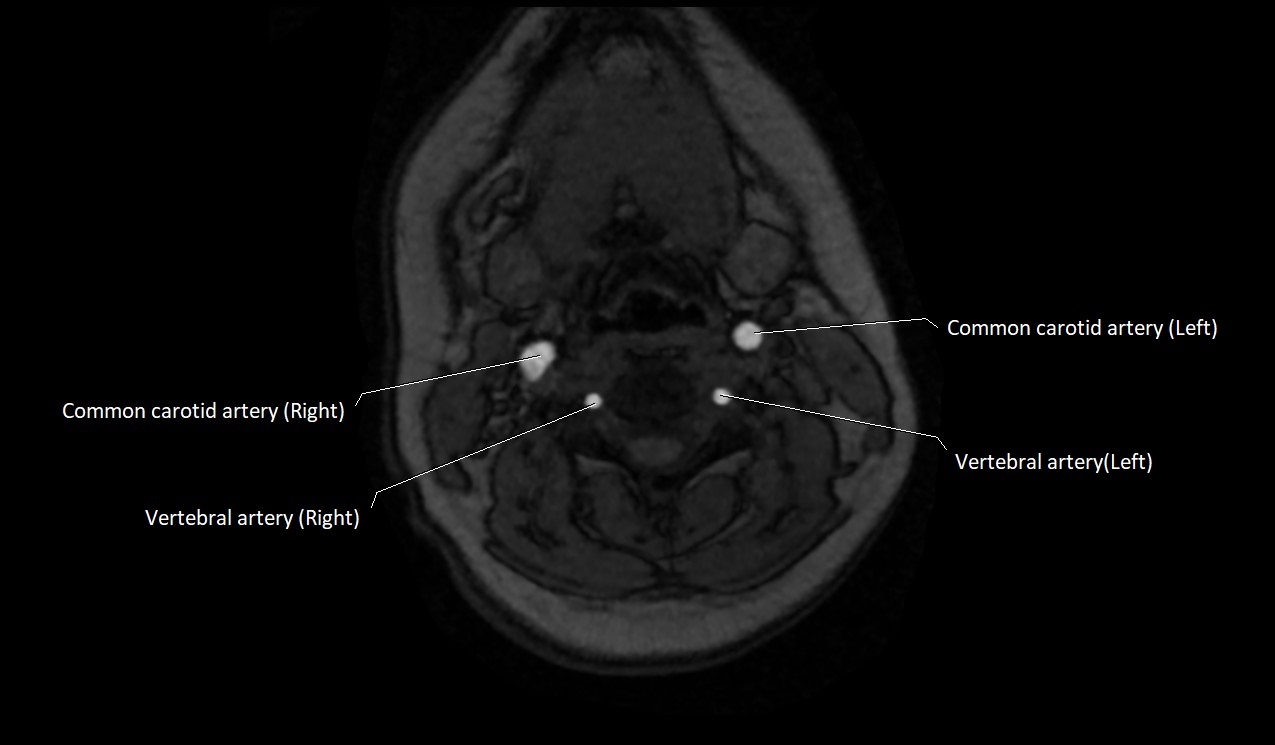

MRI images

image